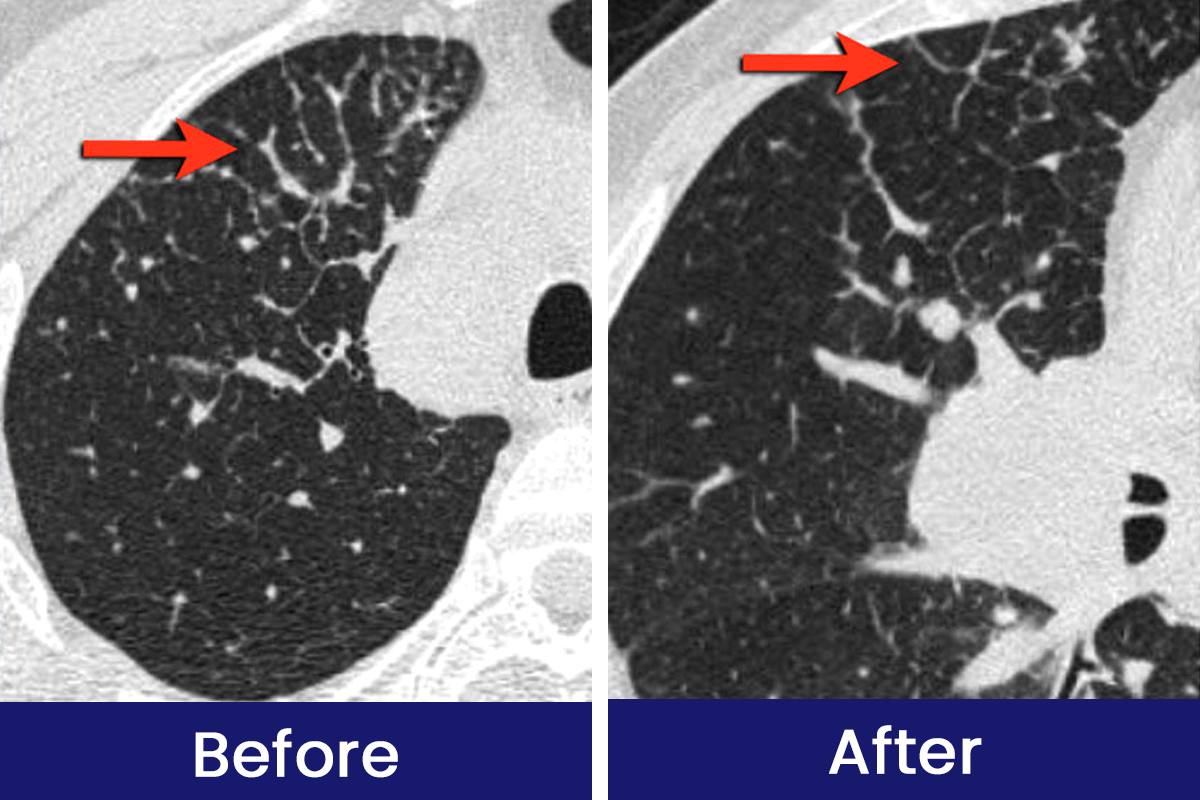

See How Luhaka™ Nicofree is Helping Customers Breathe Easier and Live Smoke-Free Every Day!